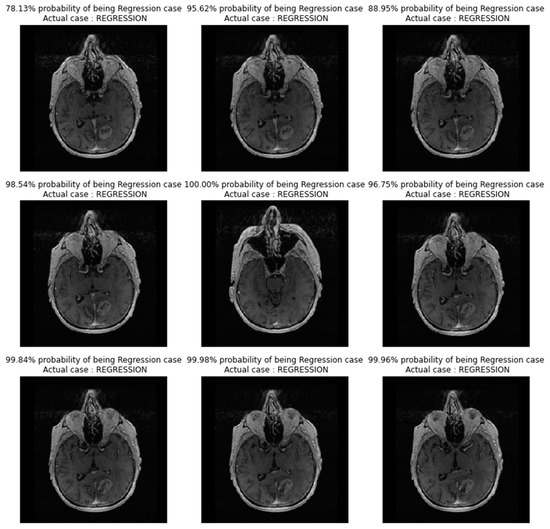

In Figure 10, images showing actual cases versus the predicted cases, with probability of prediction, for the FT_model on unseen images, are presented.

Figure 10. Images showing actual cases versus the predicted cases, with probability of prediction, for the FT_model, on unseen images.